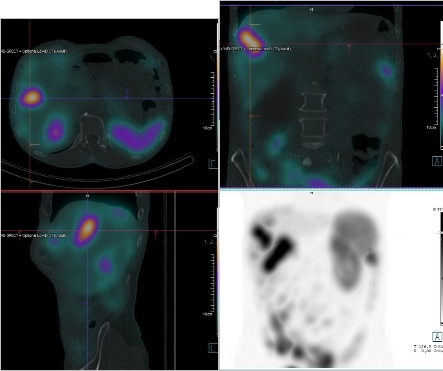

/ Obr. č. 4: Fúze SPECT/CT břicha a pánve 4 hod. po aplikaci OctreoScanu.

/

/ Obr. č. 5: Fúze SPECT/CT břicha a pánve 4 hod. po aplikaci OctreoScanu.

Pozorujeme patologicky zvýšenou depozici radiofarmaka: nejméně čtyři ložiska v pravém jaterním laloku (ložisko s vysokou akumulací laterálně, největší ložisko vysoce akumulující oválného tvaru dorzokaudálně, další dvě malá dorzolaterálně a kraniálně), vícečetná drobná ložiska v břiše a pánvi, zřejmě v uzlinách mezenteria a na peritoneu, ložisko pod dolním okrajem sleziny.

Akumulace dále ve slezině, ledvinách a střevních kličkách představuje fyziologickou distribuci. Vedl. nález obrovská hydronefróza pravé ledviny bez akumulace.

Mnohočetná ložiska patol. depozice Octreotidu odpovídají generalizaci procesu v dutině břišní - játra, mezenterium, karcinomatoza peritonea, pod slezinou.